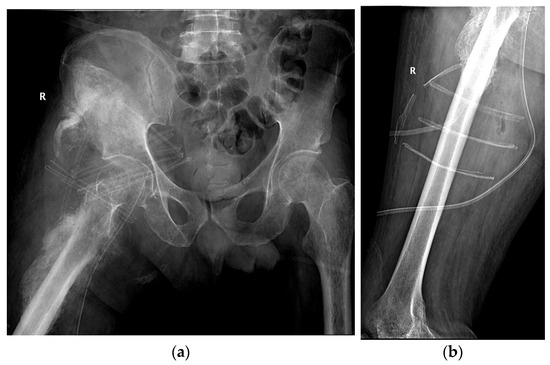

Integrated Clinical Workflow for Preoperative Planning and Resection of Giant Iliofemoral Heterotopic Ossification Using Three-Dimensional Technologies

Background/Objectives: Neurogenic heterotopic ossification (HO) is an abnormal formation of lamellar bone in soft tissues, frequently developing near major joints in patients with spinal cord injury. While imaging provides valuable diagnostic insights, large and anatomically complex HO often requires advanced preoperative planning to minimize surgical risks. This study presents the development and clinical application of a structured six-stage workflow integrating three-dimensional (3D) technologies for the preoperative planning and surgical resection of giant iliofemoral HO. Materials and Methods: A workflow was developed comprising: (1) 3D imaging acquisition, (2) creation of a virtual model, (3) production of a life-size physical model, (4) preoperative simulation, (5) surgical resection, and (6) postoperative imaging validation. The workflow was applied to a 50-year-old male with paraplegia after a T12 fracture who developed a 26 cm iliofemoral bony bridge, confirmed by computed tomography and 3D reconstruction. Results: The physical model provided a precise anatomical reference, enabling detailed surgical rehearsal and safe planning of neurovascular dissection. Resection was performed using combined orthopedic and vascular techniques. The hip joint was preserved, and postoperative rehabilitation achieved improved range of motion and patient handling without major complications. Conclusions: This structured 3D-assisted workflow enhanced anatomical understanding and surgical precision in this complex case. The framework is applicable to other extensive ossifications with intricate anatomical relationships and warrants further evaluation in larger series. Full article

Show Figures

Figure 1